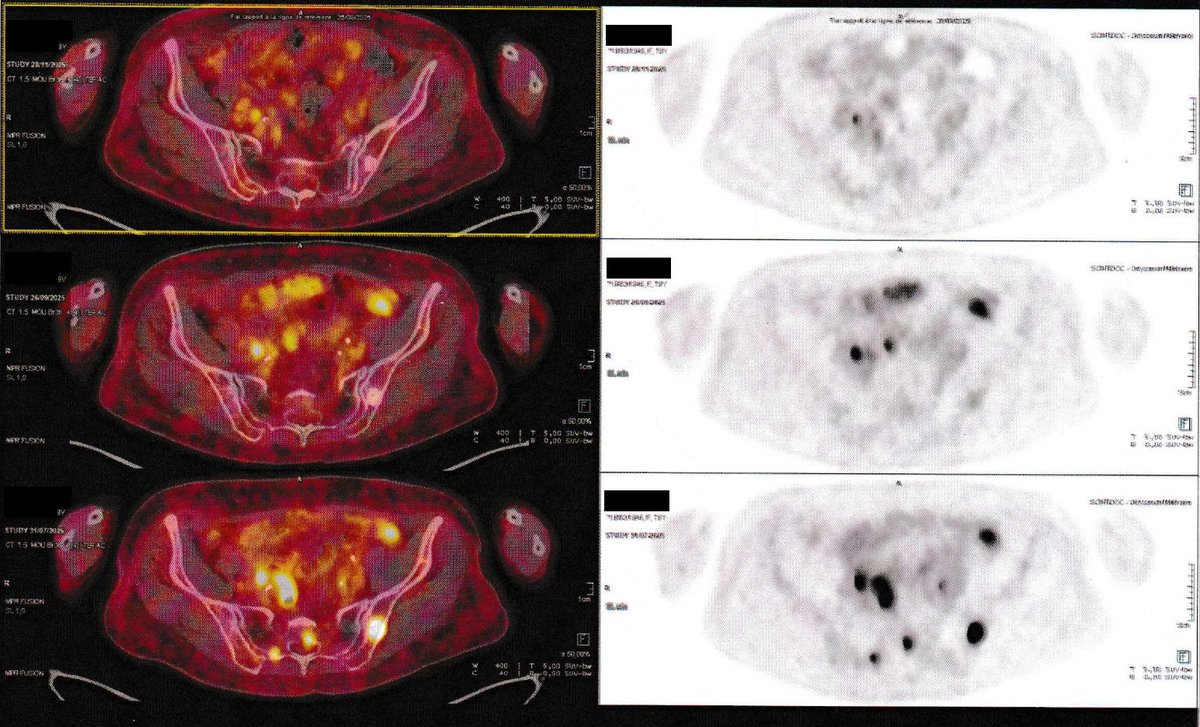

NEW ARTICLE: IVERMECTIN, MEBENDAZOLE, Vitamin B17, Graviola (Soursop) Testimonial - 79 year old woman in France with Stage 4 Ovarian Cancer achieves an impossible remission in 2 months! "Dear Dr. Zubin, I am writing to share some excellent news regarding the improvement of my